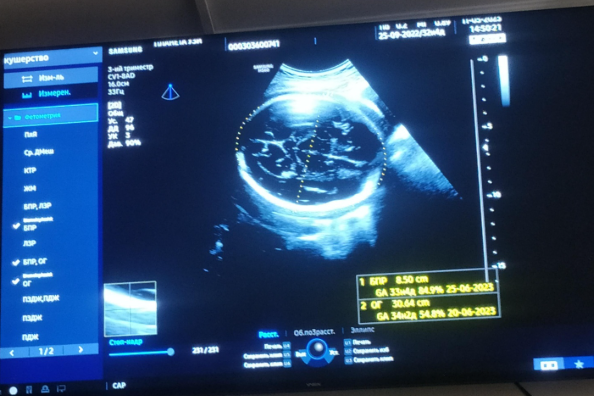

Специализация Сабитжана Каримжановича широка: от УЗИ органов брюшной полости, малого таза и щитовидной железы до высокоточного акушерского УЗИ и допплерографии сосудов плода. Однако его истинное призвание и особая миссия центра — экспертное сопровождение беременности.

«Каждое плановое обследование при беременности имеет свои строгие временные рамки. Это не просто формальность, а ключевые моменты, когда мы можем получить максимум точной информации о развитии малыша, — поясняет Сабитжан Каримжанович. — По этому четкому графику за весь период проводится три основных скрининга.

Первый скрининг (12-14 недель) — это первостепенная оценка развития, определение точного срока и исключение серьезных хромосомных аномалий.

Второй скрининг ( 19-21 неделя) — самый подробный осмотр всех органов и систем плода, когда мы детально изучаем анатомию.

Третий скрининг (30-32 недели) — оцениваем темпы роста, положение малыша, состояние плаценты и готовность к родам.

Соблюдение этого графика — основа современного, ответственного и безопасного подхода к ведению беременности. Это позволяет не упустить ничего важного и дает будущим родителям уверенность на каждом этапе».

Опыт Сабитжана Каримжановича исчисляется десятками тысяч исследований. За полтора года работы в БСМП, где за смену нужно было принять 80-100 пациентов, он отточил скорость и точность диагностики. А последующие пять лет в специализированном центре были посвящены пренатальной диагностике: здесь он провел УЗИ 30 000 пациентам, из которых 27 000 — будущие мамы. За это время было выявлено и детально описано более 2 500 патологий различного характера, что помогло своевременно принять необходимые меры.